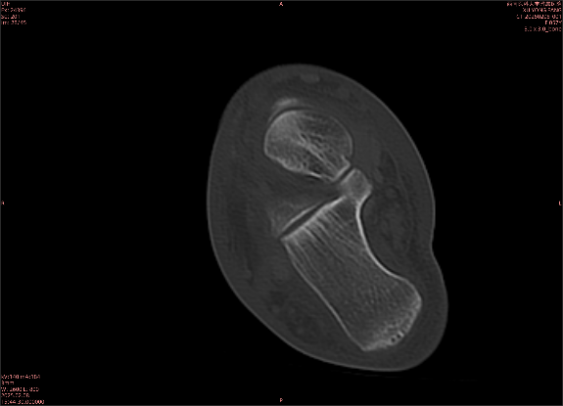

為什么DR和CT基本無法診斷?(專業(yè)科普)

由于無骨皮質(zhì)中斷,尚不足以引起X線衰減系數(shù)的明顯改變,X線平片無異常征象;CT在顯示骨皮質(zhì)及軟組織異常方面明顯優(yōu)于傳統(tǒng)X線,特別是三維重建能夠有效的評價復(fù)雜骨折,骨外傷CT檢查應(yīng)用廣泛,但CT對隱性骨折的顯示亦極為有限。

舉例圖像

圖2

專業(yè)解釋看不懂沒關(guān)系,大家看圖1和圖2就可以了,這是同一個患者跟骨的磁共振和CT圖像,圖1的紅色箭頭指示的黑線就是磁共振圖像顯示的骨折線,一目了然。而對比圖2的CT圖像上并未顯示異常。